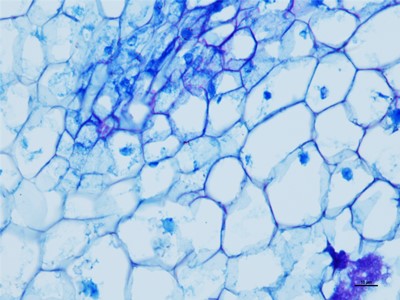

我们要在显微镜底下观察细胞的时候,就得把组织和细胞以及需要观察的东西切片,这些就得控制在厚度大概在1-10微米,这个厚度是最好观察物质的,如果没有在这个厚度之间的切片基本在观察就没有什么颜色。下面陕西依科生物技术有限公司针为大家介绍HE染色的具体操作步骤。

HE染色是基本病理的染色技术,HE染色是病理医生可以正确判断的唯一准则,首先在做实验的时候要准备乙醇、冰丙酮、苏木精染液、伊红染液、二甲苯、云南中性树胶、培养瓶、培养皿、盖玻片、载玻片、显微镜等一些器材。首先将云南石蜡切片脱蜡然后在将切片放进二甲苯无水乙醇,酒精,然后切片在放进伊红染色液中染色,然后就是将切片放入酒精和无水乙醇、二苯甲,脱水然后将切片拿出晾干,然后在封片。然后在用显微镜观察,图像采集。我们在做HE染色的实验时要注意以下细节,首先是脱蜡时要保持干净,已经苏木精染色的时间。以上就是HE染色的操作流程。